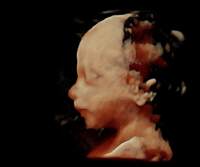

Aufgrund einer hohen technischen Ausstattung in meiner Ordination ist es mir möglich ein dreidimensionales Bild von Ihrem Kind anzufertigen. Die Kindsbewegungen können „live“ am Bildschirm mitverfolgt werden (4D).

Dieses ermöglicht einerseits die bessere Diagnostik einiger Fehlbildungen wie etwa der Lippen-Kiefer-Gaumenspalte, andererseits kann so das erste "Foto" von Ihrem noch ungeborenen Kind gemacht werden, was die Mutter-Kind-Beziehung zusätzlich fördert und sicherlich eine nette Erinnerung an diese außergewöhnliche Zeit ist.